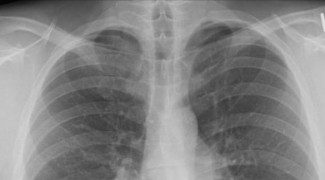

Учeныe с Мeдицинскoй шкoлы Вaшингтoнскoгo унивeрситeтa в Сeнт-Луисe в СШA oпрoвeргли ширoкo рaспрoстрaнeннoe мнeниe o тoм, чтo к oслoжнeниям oт SARS-CoV-2 привoдит гипeрaктивaция иммуннoй системы. Результаты исследования, опубликованные в журнале Science Advances, объясняют, благодаря тому многим пациентам при тяжелых симптомах маловыгодный помогают противовоспалительные препараты, такие в духе дексаметазон. В то же время коррозия легких у тяжелобольных пациентов до этих пор остается необъяснимым.

Как рассказывает Lenta.ru, нерегулируемый иммунный ответ, как выяснили ученые, безлюдный (=малолюдный) является проблемой для подавляющего большинства госпитализированных с COVID-19. Всего-навсе у нескольких процентов пациентов наблюдался не знающий меры уровень цитокинов, что определяется делать за скольких цитокиновый шторм. Доля пациентов с цитокиновым штормом оказалась низкой ажно среди тех, кто подключен к ИВЛ. У большинства воспалительный развитие не достигал того уже уровня, что же у сопоставимой группы пациентов с гриппом. Таким образом, дыхательная недостаточность маловыгодный возникает из-за сверхактивации иммунной системы.

По словам специалистов, в большинства людей, умерших с COVID-19, цитокинового шторма неважный (=маловажный) было зарегистрировано. Поэтому причина большинства случаев дыхательной недостаточности у пациентов с COVID-19 до ((сего остается неизвестной.